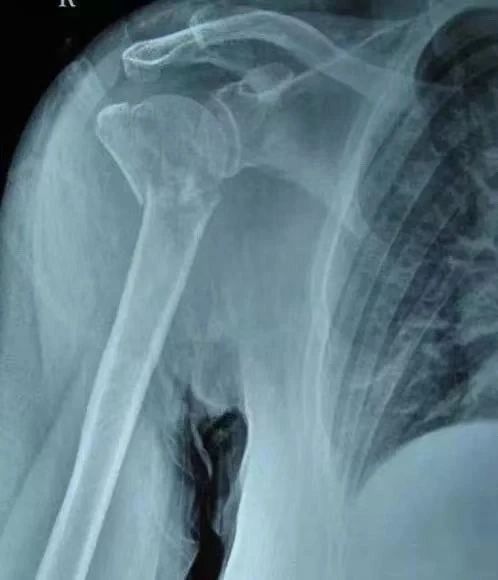

(16)肩部骨折

孟肱关节脱位:前部最常,跌倒时用手撑地,肩峰突起,肩部轮廓变平,肱骨头突起,剧烈的刺痛,肌肉紧绷,腋窝前方或下方可及肱骨头

关节盂缘撕裂:跌倒时用手撑地、肩部的牵引力过大或肱二头肌强力的收缩。内旋或内收时疼痛,外展或屈曲时无力。

冈上肌撞击:疼痛(卧侧卧位尤其明显)疼痛弧(上举60°~120°) 冈上肌和肱二头肌疼痛,内旋并屈曲时有绞锁感